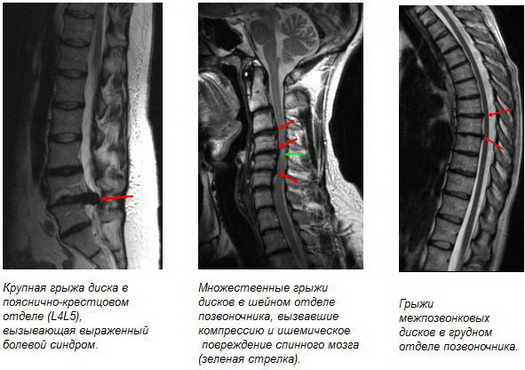

Картина МРТ при межпозвонковых грыжах

- межпозвонковые грыжи;

- Формирование грыжи межпозвонковых дисков с указанием стадии процесса:

- Протрузия – разрыв волокон фиброзного кольца с выходом наружу части желеобразного пульпозного ядра. На этой стадии размер грыжи составляет 2-3 мм.

- Частичный пролапс — вторая стадия развития грыжи, характеризующаяся увеличением участка выпячивания тканей до 10 мм. В области пораженного межпозвонкового диска наблюдаются нарушение кровообращения и отек нервного корешка.

- Полный пролапс — третья стадия развития заболевания: пульпозное ядро выходит за пределы диска, но сохраняет свою целостность. Размер грыжи может достигать полутора сантиметров.

- Секвестрация — четвертая стадия формирования грыжи. Пульпозное ядро выдавливается (выпадает) в спинномозговой канал, его фрагмент (секвестр) отрывается от основной массы и защемляет нервы, идущие от позвоночника к внутренним органам и конечностям.

Секвестрированные межпозвонковые грыжи (свободно лежащие фрагменты обозначены стрелками)

• грыжи межпозвонковых дисков, как проявление остеохондроза, являющиеся наиболее частой причиной болей в шейном отделе позвоночника с возможной иррадиацией в плечевые суставы, верхние конечности и голову;

• крупные грыжи дисков, оказывающие давление на спинной мог и нервные корешки, а также вызывающие ишемическое их поражение, что в свою очередь приводит к нарушениям чувствительности и двигательной функции верхних конечностей;

• грыжи межпозвонковых дисков, вызывающие боли в пояснично-крестцовом отделе позвоночника с возможной иррадиацией в тазобедренные суставы, нижние конечности, органы малого таза или приводящие к нарушению чувствительности и двигательной дисфункции нижних конечностей и тазовых органов;